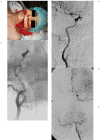

Vascular injury is an unusual and serious complication of transsphenoidal surgery. We aimed to define the role of angiography and endovascular treatment in patients with vascular injuries occurring during transsphenoidal surgery. During the last ten-year period, we retrospectively evaluated nine patients with vascular injury after transsphenoidal surgery. Eight patients were symptomatic due to vascular injury, while one had only suspicion of vascular injury during surgery. Four patients presented with epistaxis, two with subarachnoid hemorrhage, one with exophthalmos, and one with hemiparesia. Emergency angiography revealed a pseudoaneurysm in four patients, contrast extravasation in two, vessel dissection in one, vessel wall irregularity in one, and arteriovenous fistula in one. All patients but one were treated successfully with parent artery occlusion, with one covered stent implantation, one stent-assisted coiling method, while one patient was managed conservatively. One patient died due to complications related to the primary insult without rebleeding. Vascular injuries suspected intra or postoperatively must be investigated rapidly after transsphenoidal surgery. Endovascular treatment with parent artery occlusion is feasible with acceptable morbidity and mortality rates in the treatment of vascular injuries occurring in transsphenoidal surgery.